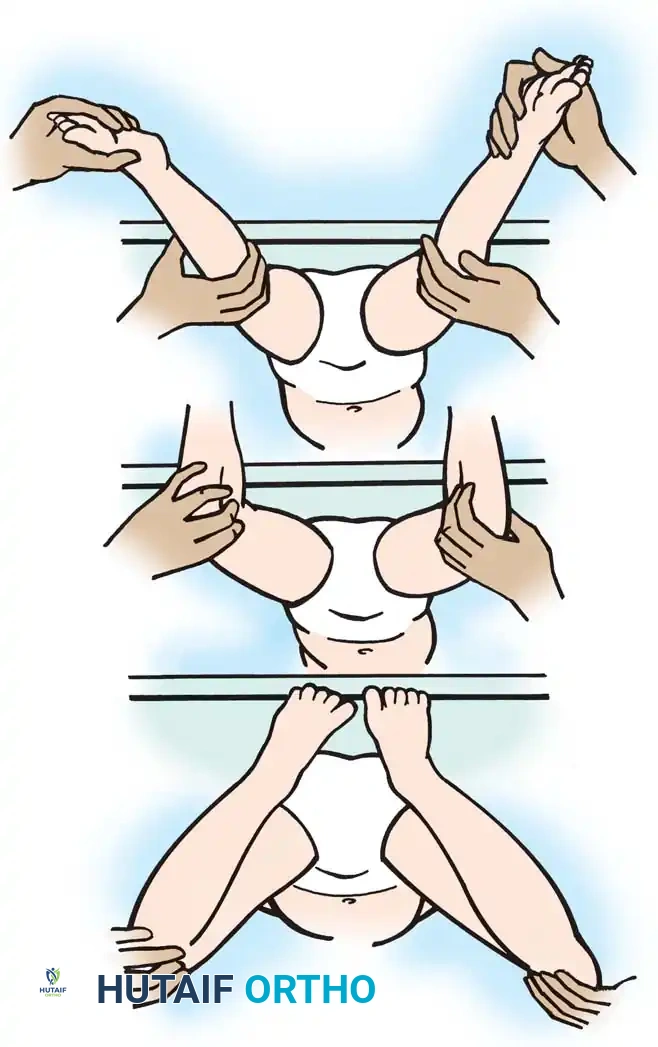

Adductor and Medial Hamstring Assessment

To isolate medial hamstring spasticity, the patient is examined supine with the knees flexed over the edge of the table. This position relaxes the hamstrings proximally, allowing the hip to be abducted (provided there is no primary adductor contracture). If full knee extension is impossible unless the hip is adducted, tightness in the medial hamstrings and gracilis is confirmed.

Fig. 30-21 Testing for adductor and medial hamstring tightness. A, Thighs abduct well with hips and knees flexed, indicating no adductor contracture. B, With hips extended and knees flexed, hips abduct well. C, With hips extended, bringing knees into extension causes thighs to adduct, indicating medial hamstring spasticity.